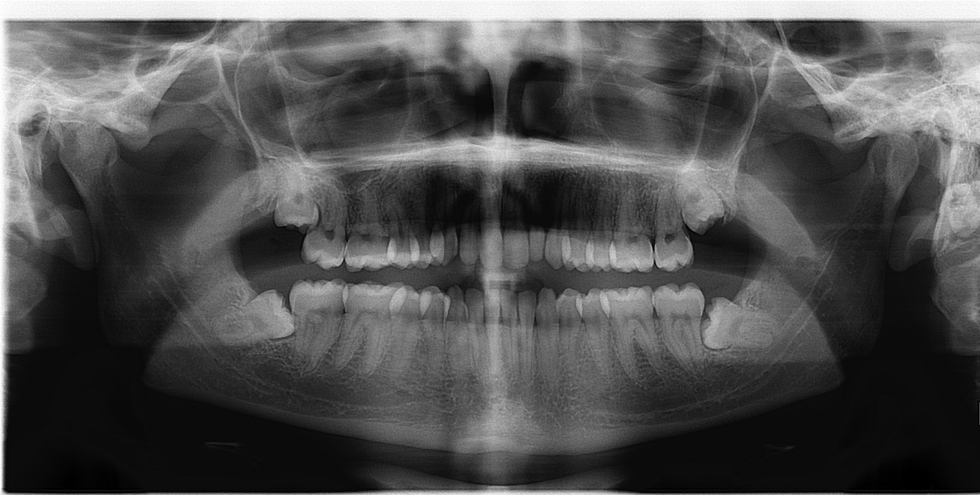

For example, while all of my other friends were getting shwasted and frolicking around during Spring Break 2017, I spent the sweet time getting my wisdom teeth yanked out of my mouth. This is purely because I am graduating early, and I have no other time to fit this procedure into my schedule, so I gotta do what I gotta do.